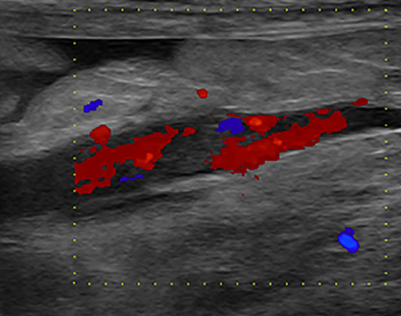

오직 완전 폐색인지, 불완전 폐색인지가 유일한 예후 평가의 기준이라고 보면된다. 즉, 혈전의 side 로 미세하게 흐름이 존재하는지가 중요하다는 말.